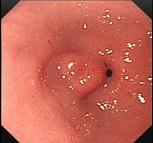

问题 男,70岁,剑突下疼痛伴进行性咽下困难1个月,消瘦、乏力明显,粪隐血持续阳性,内镜及影像检查如下图,诊断为 ( )

选项 A.胃黄斑瘤 B.贲门息肉 C.胃溃疡 D.贲门癌 E.胃癌

答案 E